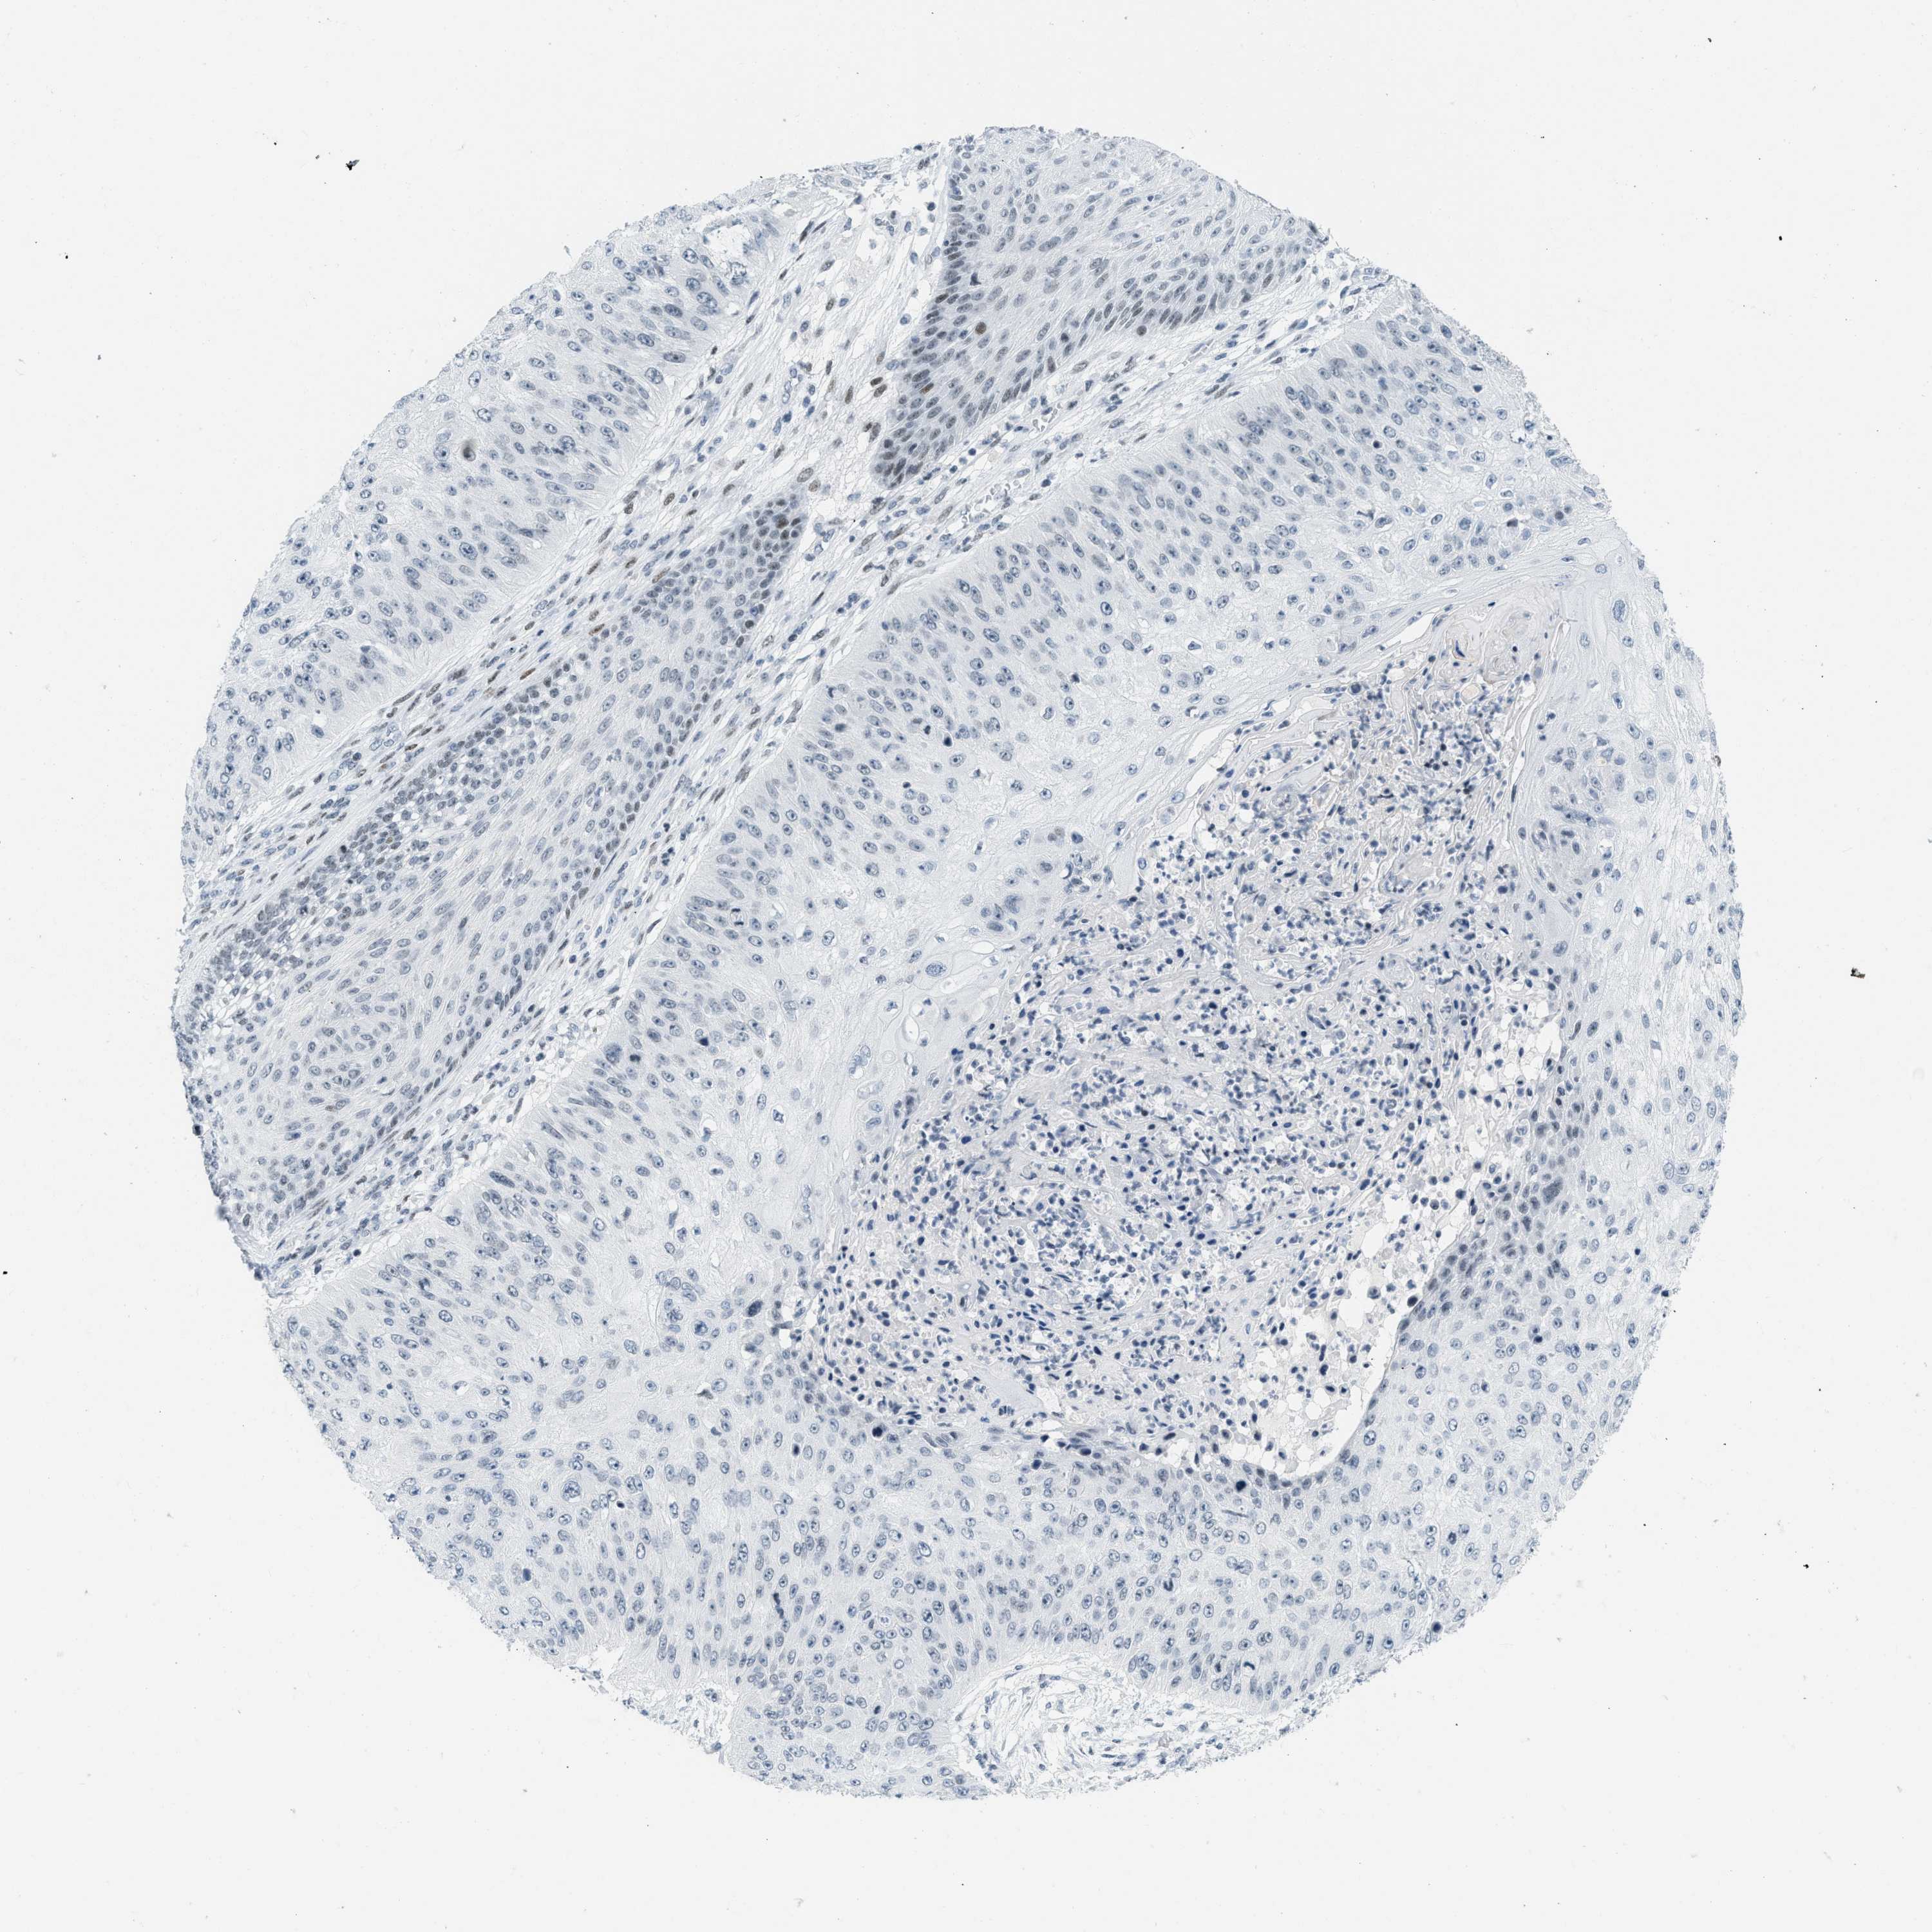

SKIN CANCER - Protein expressioni

A mouse-over function shows sample information and annotation data. Click on an image to view it in a full screen mode. Samples can be filtered based on level of antibody staining by selecting one or several of the following categories: high, medium, low and not detected. The assay and annotation is described here.

Each image is clickable and will lead to virtual microscopy that enables deeper exploration of all samples and also displays staining intensity scores, fraction scores and subcellular localization as well as patient and tissue information for each sample.

Antibody HPA003505

Squamous cell carcinoma, NOS

Basal cell carcinoma

Squamous cell carcinoma in situ, NOS

Squamous cell carcinoma, metastatic, NOS